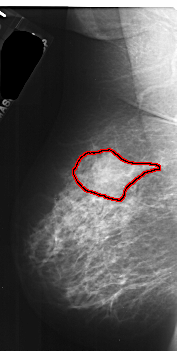

FILE: A_1036_1.LEFT_MLO.OVERLAY

TOTAL_ABNORMALITIES 1

ABNORMALITY 1

LESION_TYPE MASS SHAPE IRREGULAR MARGINS ILL_DEFINED

ASSESSMENT 4

SUBTLETY 5

PATHOLOGY MALIGNANT

TOTAL_OUTLINES 1

BOUNDARY